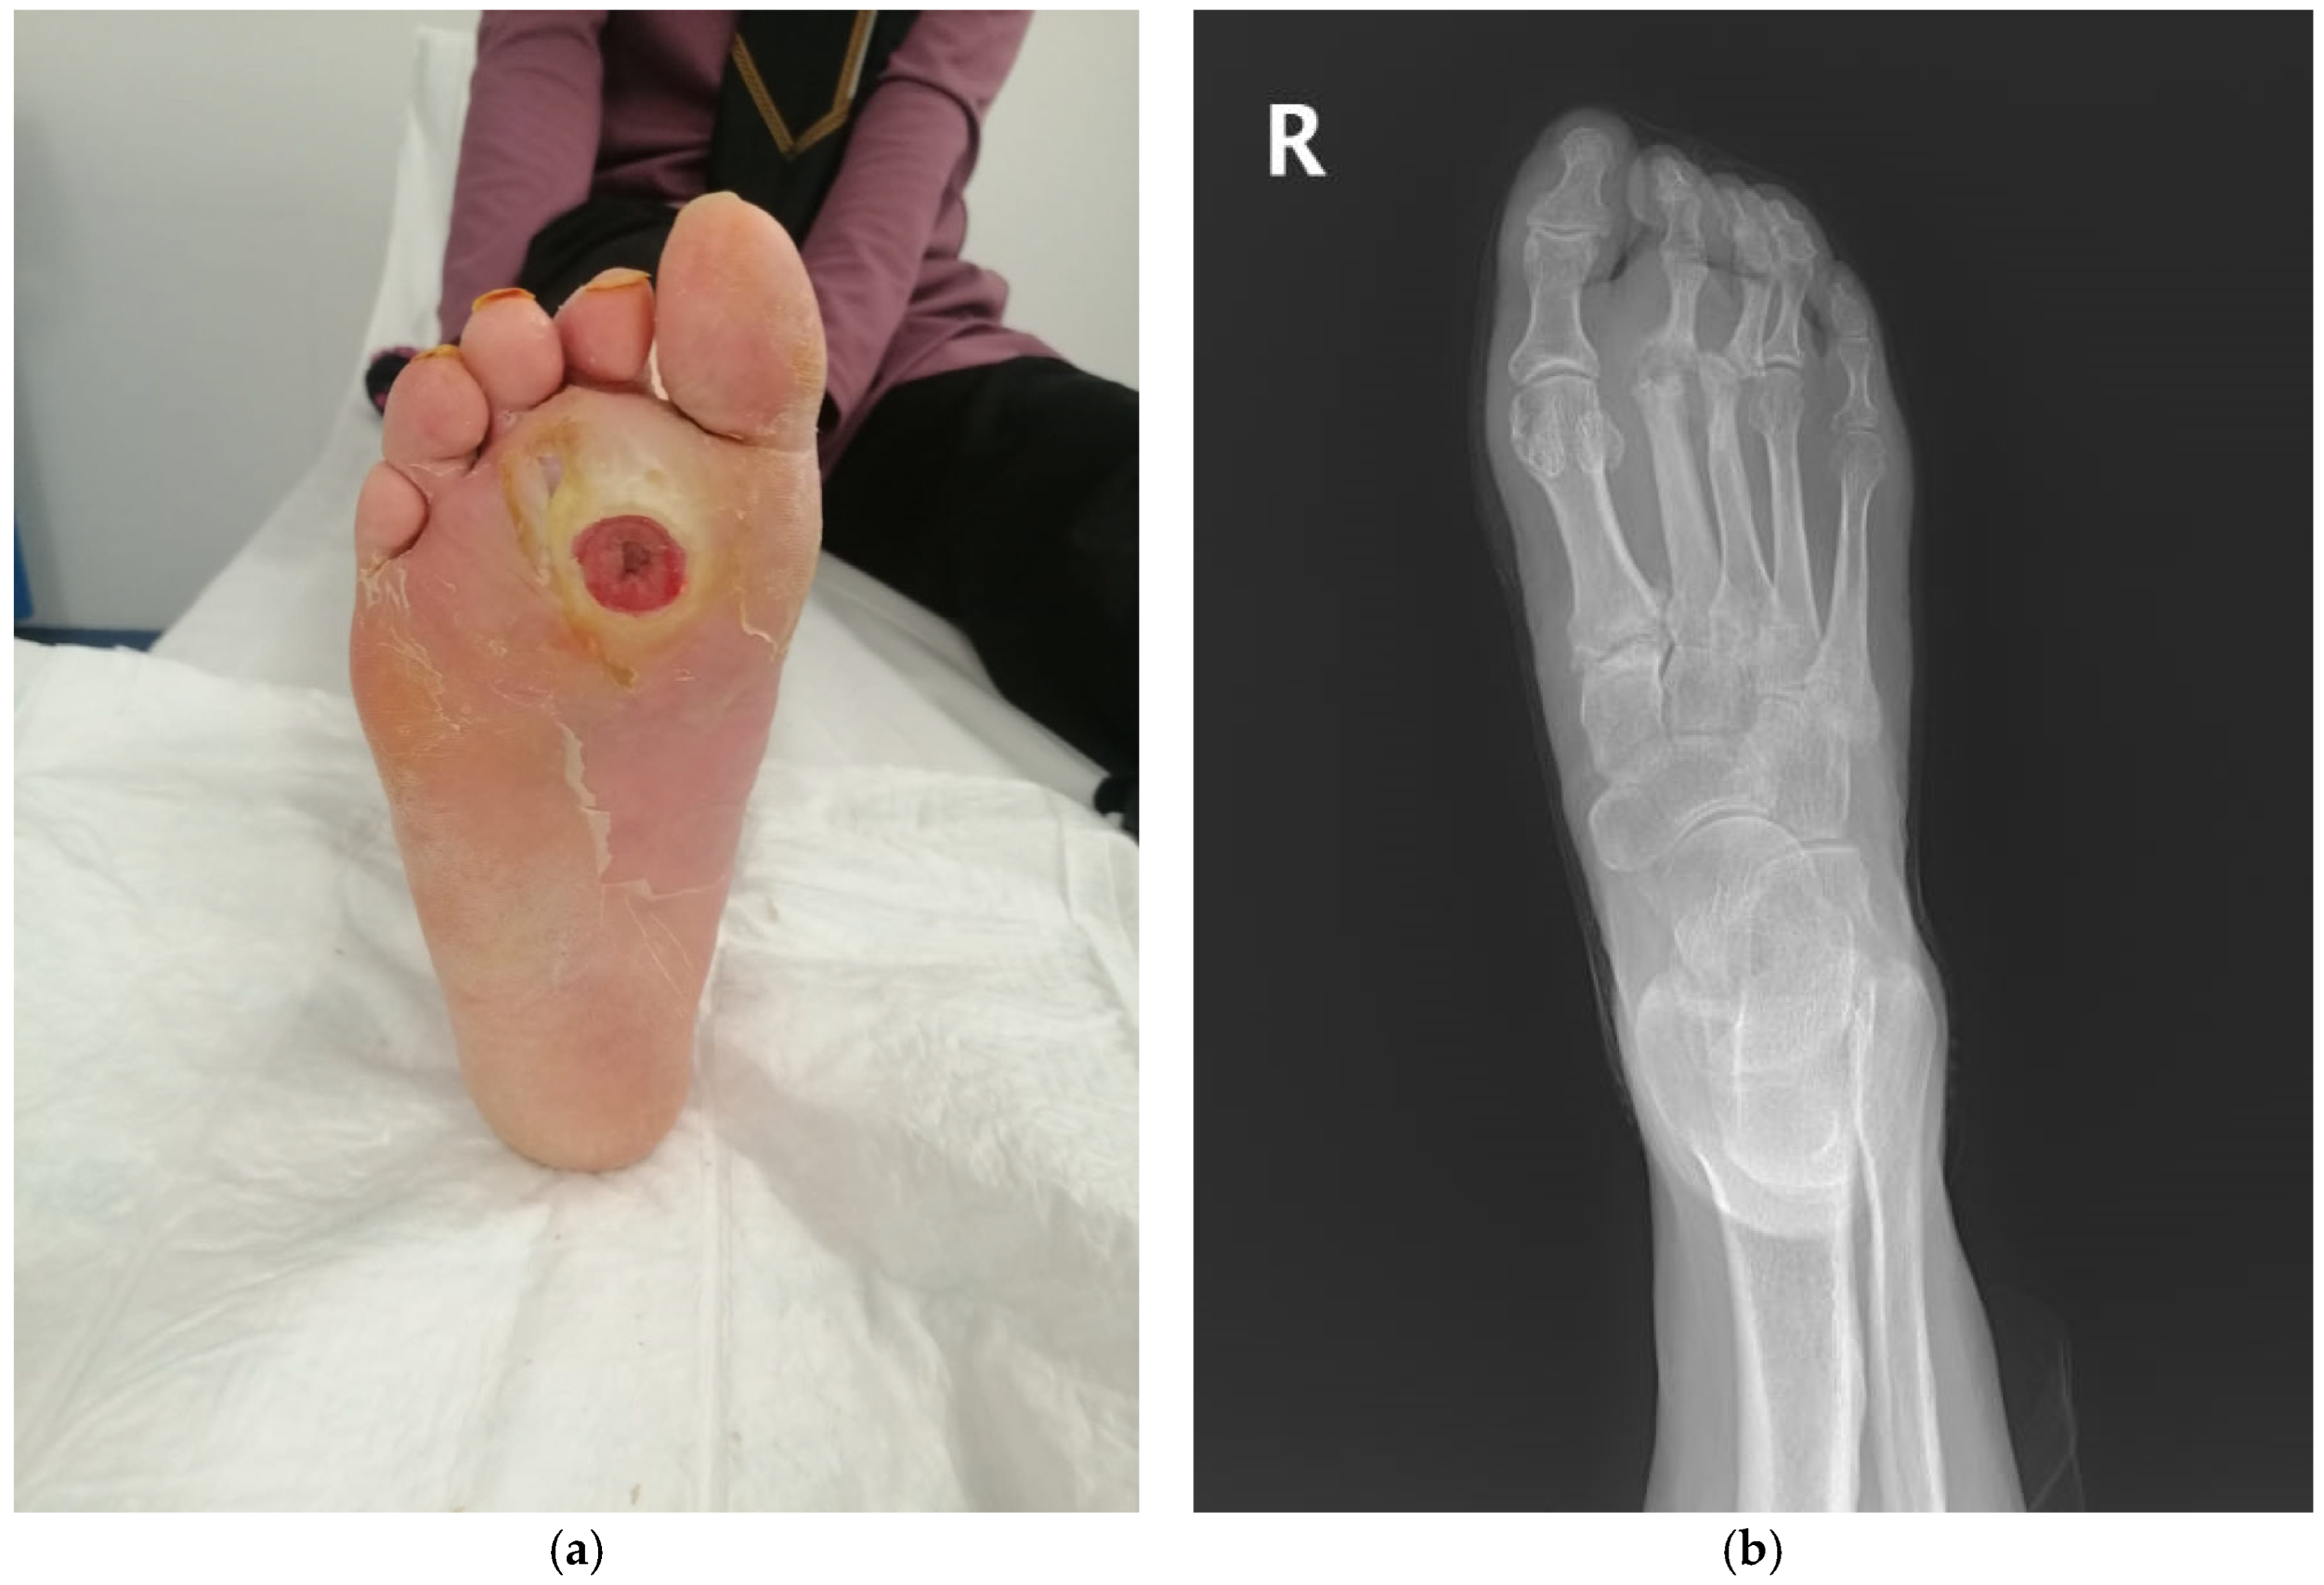

- Clinical diagnosis of diabetic foot infection (DFI);

- Positive probe-to-bone (PTB) test (defined as palpable bone through the ulcer using a sterile blunt metal probe);

- Radiographic findings consistent with osteomyelitis on initial or follow-up X-rays;

- Underwent surgical intervention (debridement or amputation) during which deep tissue and bone culture samples were intended to be collected simultaneously;

- If bone culture could not be obtained intraoperatively due to technical limitations, patients were still included provided that osteomyelitis was supported by both clinical and radiological evidence;